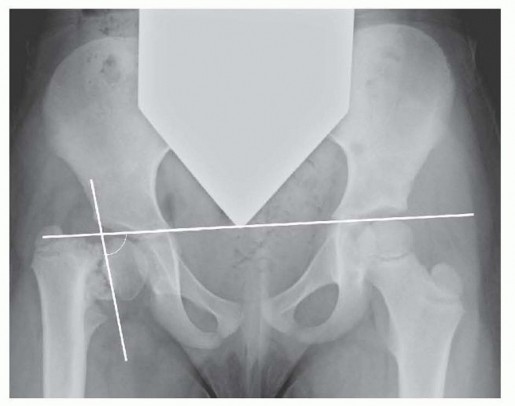

Triple Innominate Osteotomy DEFINITION Triple innominate osteotomy (TIO) is a surgical procedure that include…